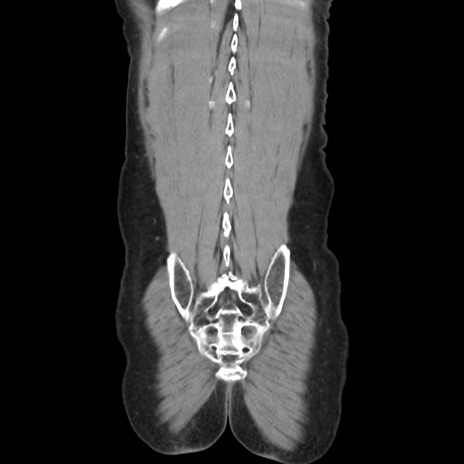

横断像